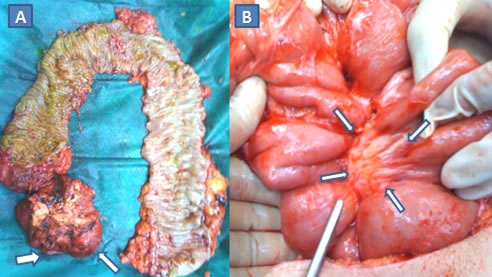

Εικόνα 1.

Α. Έμμισχος σωληνολαχνωτός αδενωματώδης πολύποδας που αφαιρέθηκε χειρουργικά.

Β. Ευμεγέθης άμισχος λαχνωτός αδενωματώδης πολύποδας ορθού που αφαιρέθηκε χειρουργικά διά του ορθού.

(Από το προσωπικό αρχείο του Γ. Θεοδωρόπουλου)